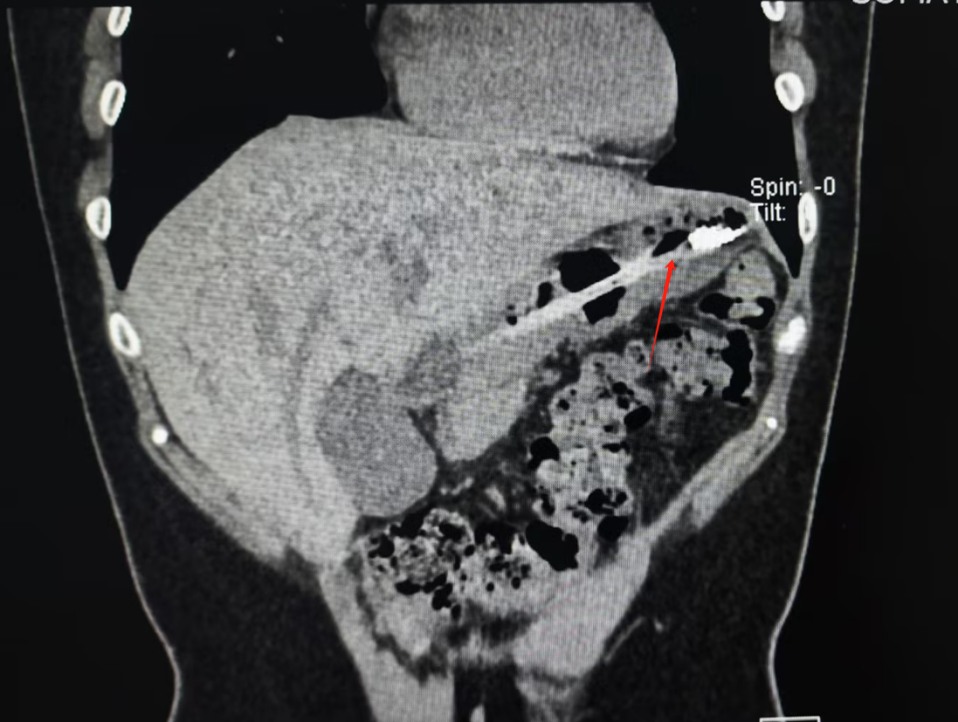

结果,因为反复的暴饮暴食,让小李感觉胃胀、胃痛、反酸、打嗝,出现了明显消化不良的表现,同时大量进食也让她产生了深深的身材焦虑。结果小李选择了催吐来缓解胃不适和长胖焦虑。为效果更好,该女子用一次性牙刷作为工具,结果手打滑,18cm长牙刷顺着咽喉直接滑了下去。 幸运的是,由于女子就医及时,在医生的帮助下牙刷顺利取出,并未对胃壁造成严重的损伤。

成都市中西医结合医院消化内科王晓翔医生表示,牙刷这种异物掉入胃中并不常见,而且牙刷的硬度和形状可能会对胃壁造成划伤、穿孔等损伤,还好患者来得及时,如果牙刷继续掉入肠道,还可能引起肠梗阻等严重后果。

图:胃中取出的牙刷